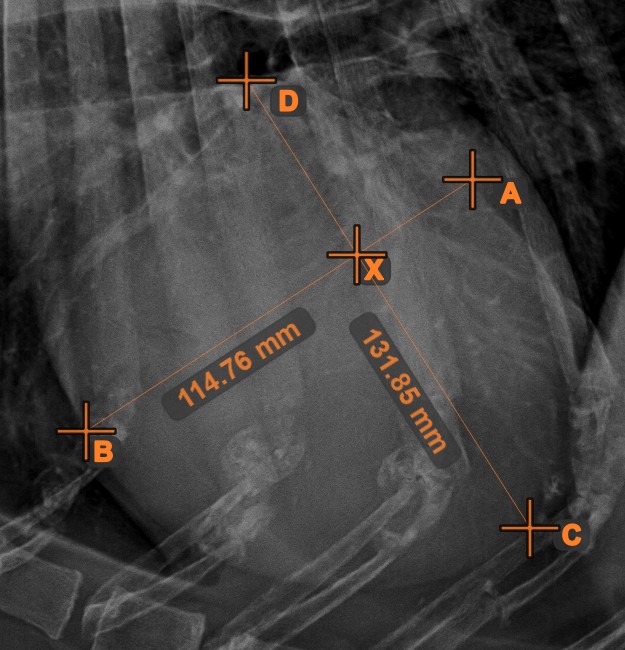

Vonalak metszéspontja¶

Gyorsan és pontosan találja meg és jelölje két meglévő vonal közti metszéspontot a Vonalak metszéspontja eszközzel.

Válassza ki az eszközt a bal oldali eszköztárból, és rendelje hozzá az egyik elérhető egérgombhoz. Válasszon ki két, a jelenetben már meglévő vonalat a mérés elvégzéséhez. A vonalak metszéspontja automatikusan kiszámításra kerül és jelölésre kerül a jelenetben. Két vonal metszéspontját mindig az X betű jelzi.

Információ

Ha két vonal közvetlenül nem metszi egymást, a jeleneten azok meghosszabbított vetületeinek metszéspontja lesz jelölve.